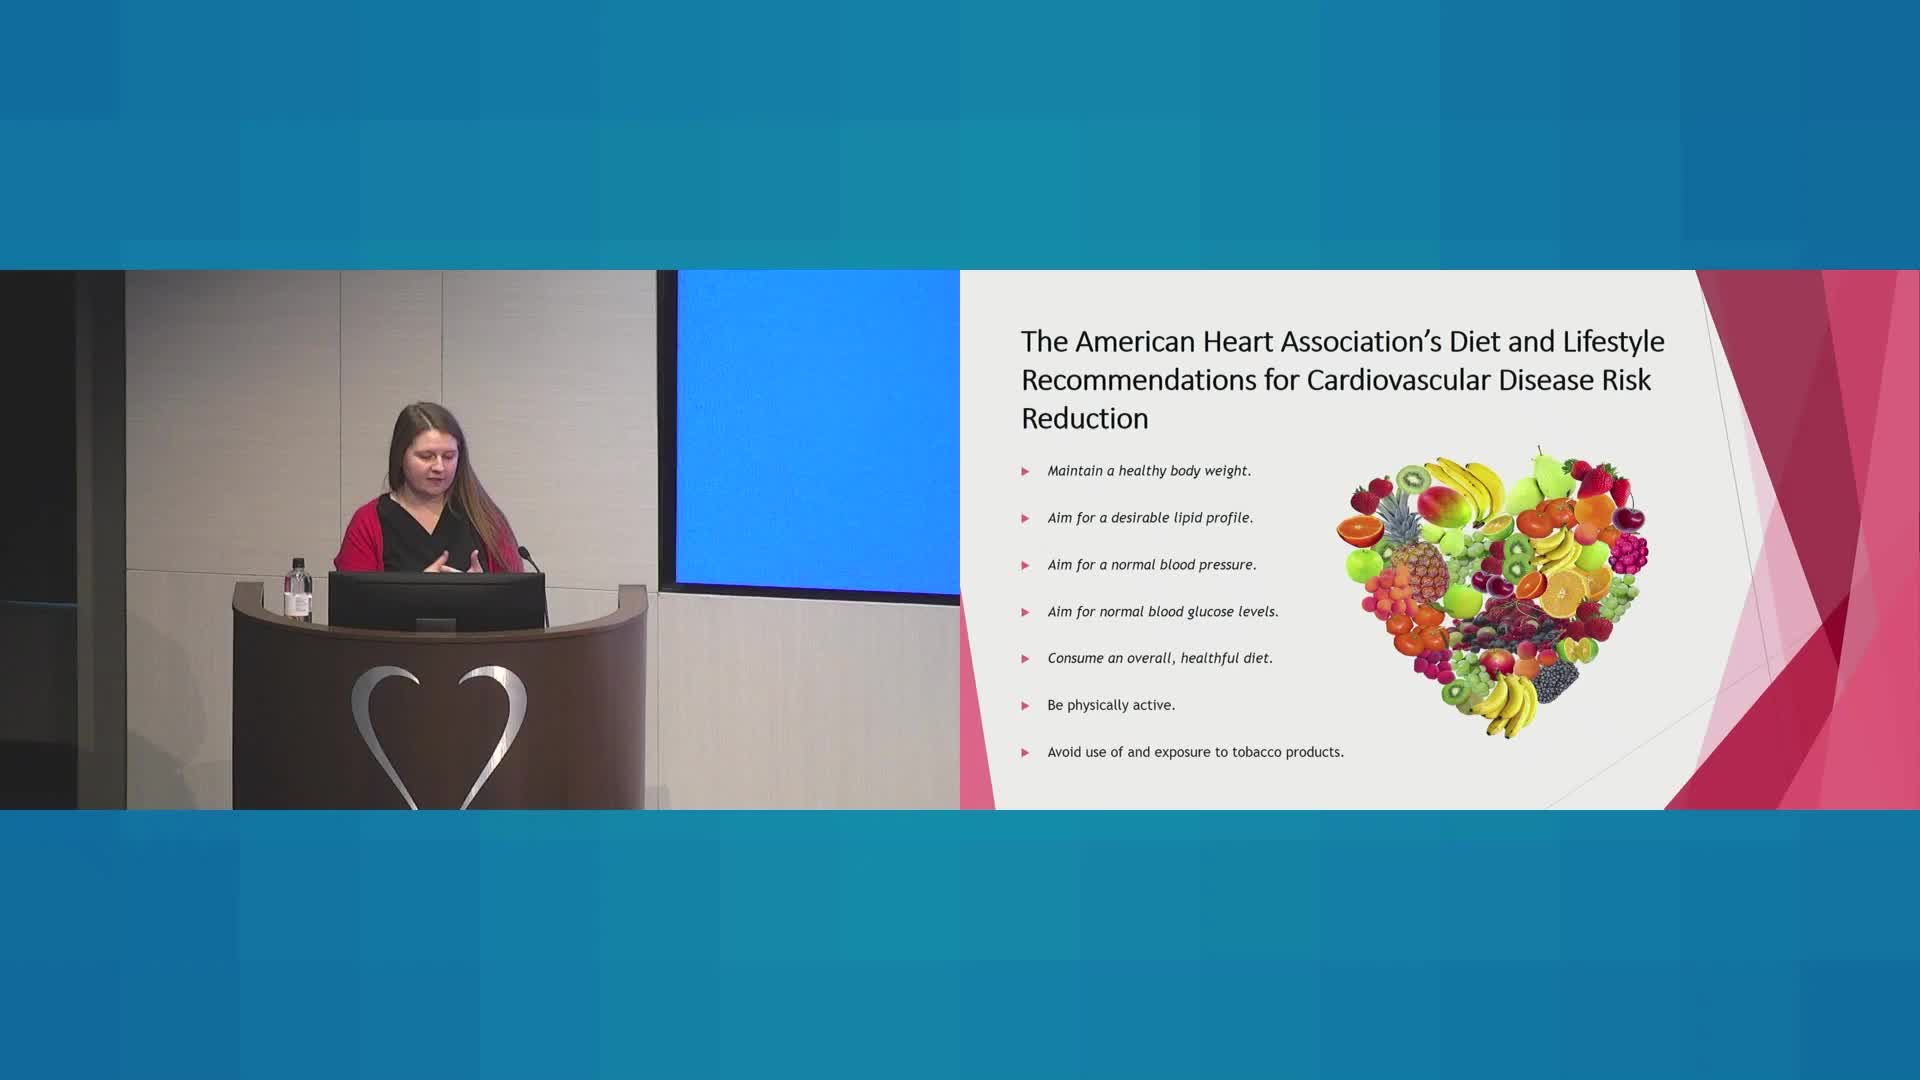

Our mission is to provide a collaborative environment and educational opportunities for physicians, scientists, nurses, and medical professionals to discuss and teach advanced techniques, improve clinical knowledge, and enhance the ability to provide excellent patient care, which ultimately improves patient health outcomes. To that end, the education program has strived to meet this goal educating and training the local, regional, and national medical community on the most recent advancements in medical science and research.